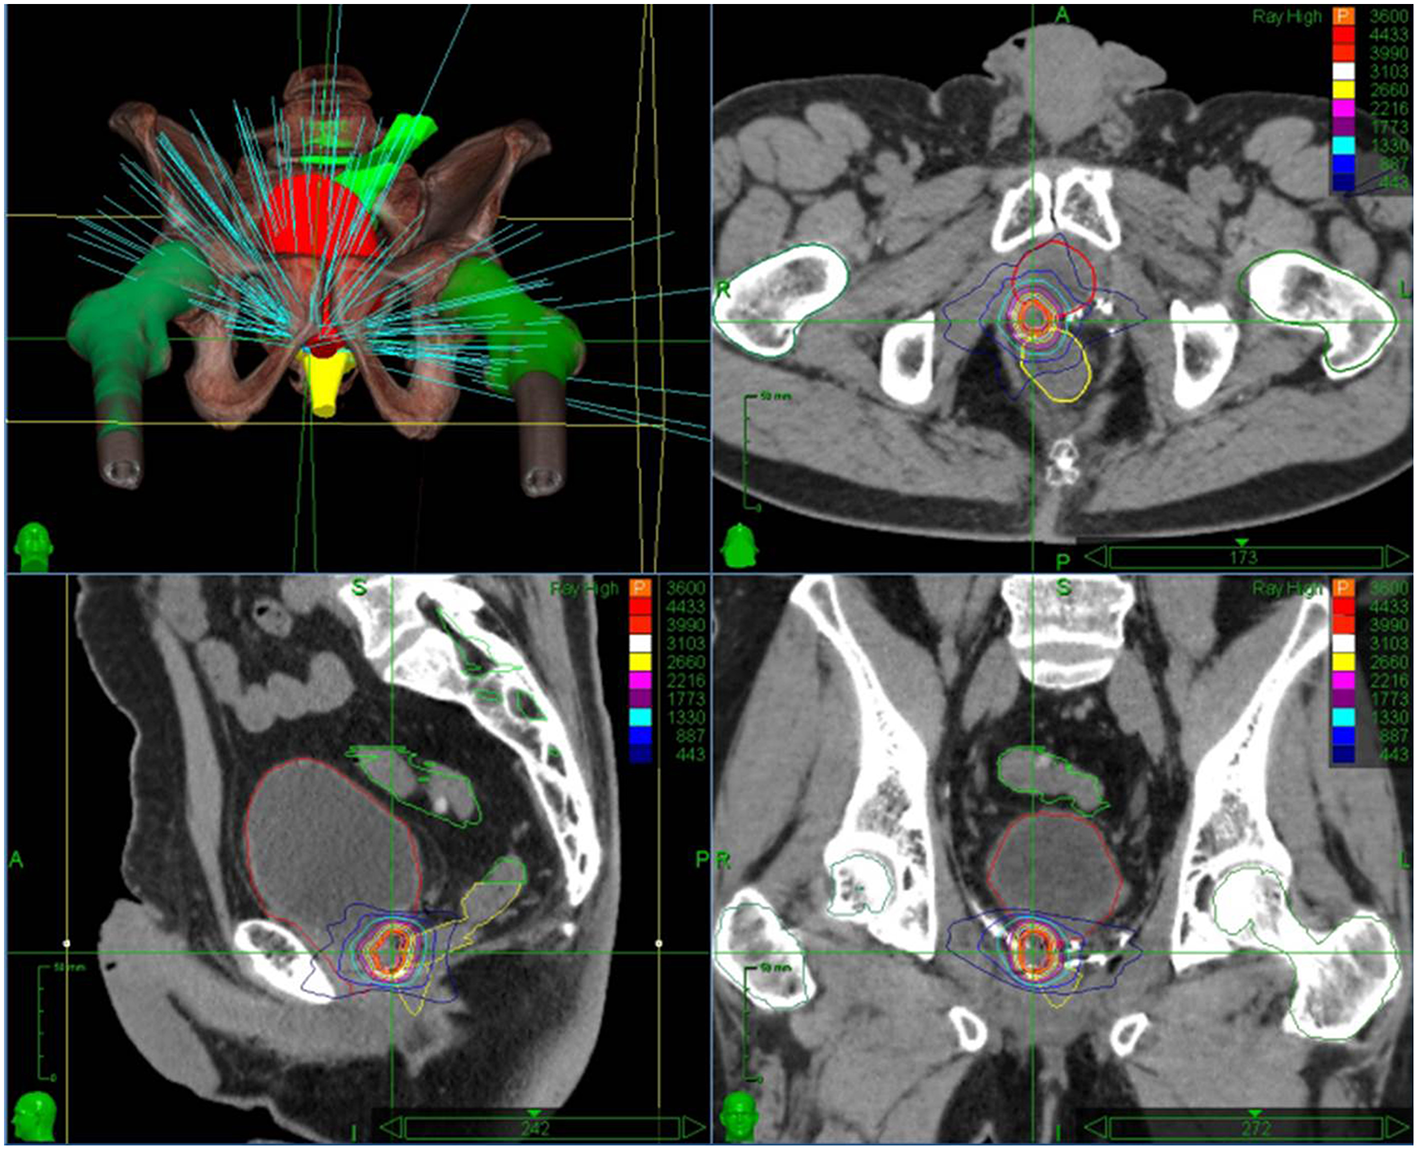

CyberKnife radiotherapy for macroscopic relapse in the prostatic bed was delivered for all patients. A total dose of 36 Gy was prescribed to the 80% isodose line (95% planning target volume, PTV, coverage) in 6 fractions of 6 Gy on alternating days (Figure 1). One internal gold fiducial was placed in contact with the lesion by an uro-radiologist with the help of MRI/ultrasound (US) fusion software. The fiducial was used for tracking the translational movements of the target lesion during SBRT. Delineation was made on a planning CT scan that was registered with the pre-treatment MRI (when the fiducial was visible on MRI) and the PET-CT to help with delineating the gross tumor volume (GTV). GTV was defined as macroscopic local recurrence on imaging. CTV corresponded to GTV. PTV was obtained from a 2 mm margin applied to CTV. Normal tissue constraints used for the planning were for the rectum V12 < 20%, V27 < 2cc, and for the bladder V12 < 15%,V27 < 5cc. These constraints were used for prostatic re-irradiation (16) and are actually used in a GETUG phase 2 protocol of prostatic re-irradiation 1. Priority was given to the respect of the normal tissue constraints used. PTV coverage was sacrificed if necessary.

Figure 1

Stereotactic body radiation therapy treatment plan with dose distribution for an isolated macroscopic recurrence in the prostatic bed.